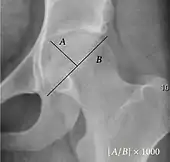

Acetabular depth ratio Deepness of acetabulum.

• The width is measured between the inferior margin of the teardrop and the lateral rim of the acetabulum.[11]

• The depth is measured perpendicularly from the midpoint of the width line.[11]

>250

• Less indicates a dysplastic hip